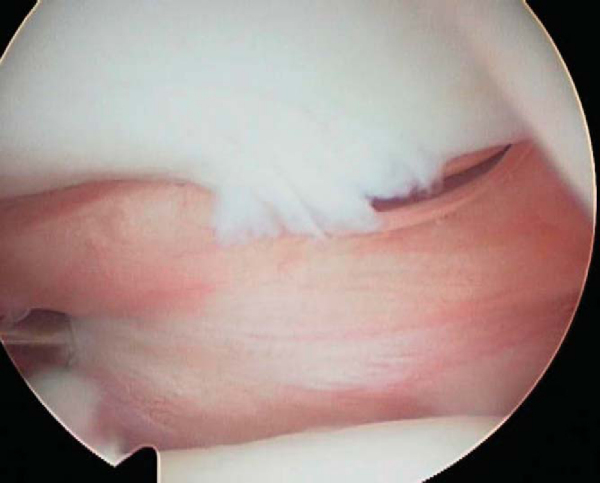

The chondral lesion is identified (

Fig. 51-2

), and the defect and its borders are carefully and systematically palpated with a blunt probe. This will expose loose flaps and any areas of delamination. It is also important to identify areas where the cartilage is softened (

Fig. 51-3

); but if the cartilage has an intact surface, it should not be débrided. Once loose flaps of cartilage are identified, a 4.5-mm aggressive shaver is placed, and the loose flaps and debris are mechanically removed until stable borders are obtained (Figs. 51-4 and 51-5 [4] [5]). A whisker-type shaver may also be used for less aggressive débridement. Care must be taken not to peel off the articular cartilage but only to remove the unstable borders. The posteromedial and posterolateral gutters are also visualized to evaluate for intraarticular loose bodies. The blunt arthroscopy obturator is placed through the notch into the posterolateral and posteromedial recess of the knee under direct visualization. Once it is in position, the camera is then placed into the obturator sleeve, and the posterolateral and posteromedial notch recesses are visualized.

Figure 51-2 |